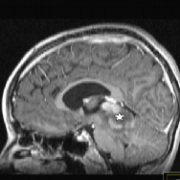

脊髓是一種少見的實(shí)體,是在兒科患者,暴露的癥狀大多是進(jìn)展性感覺運(yùn)動(dòng)和自主神經(jīng)功能缺損,繼發(fā)于脊髓內(nèi)多束受累...

原發(fā)性脊髓星形細(xì)胞瘤治療金標(biāo)準(zhǔn)是手術(shù)切除。二線治療包括放化療,輔助治療的較好方案尚未明確,巴特朗菲教授2021年2月將來華,國內(nèi)患者可預(yù)約咨詢其前沿治療方案...

神經(jīng)節(jié)膠質(zhì)瘤 是一種中樞神經(jīng)系統(tǒng)的腫瘤,懷疑起源于錯(cuò)構(gòu)瘤性神經(jīng)膠質(zhì)神經(jīng)病變的常見前體細(xì)胞。組織病理學(xué)上,這些腫瘤由神經(jīng)節(jié)細(xì)胞和膠質(zhì)細(xì)胞組成。它們在全部小兒中樞神經(jīng)系...

原發(fā)性顱內(nèi)間變性神經(jīng)節(jié)膠質(zhì)瘤在小兒患者中是少見的腫瘤。他們中的大多數(shù)表現(xiàn)為血壓升高或癥狀性癲癇,巴特朗菲教授2021年2月將來華為國內(nèi)患者解答病情...

英文摘要:Primary intracranial anaplastic gangliogliomas are rare tumors in the pediatric patient group.Most of them present with symptoms of elevated pressure or symptomatic epilepsy.Extraaxial location is far more common than axial loc...